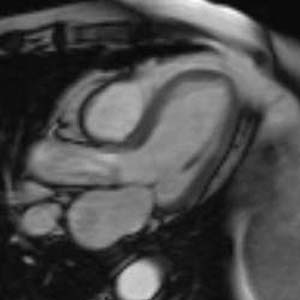

The coronary arteries can be indirectly evaluated by assessing myocardial function in the territory perfused by a given artery.

Mouse over each image to display the typical perfusion territories.

4 chamber view |